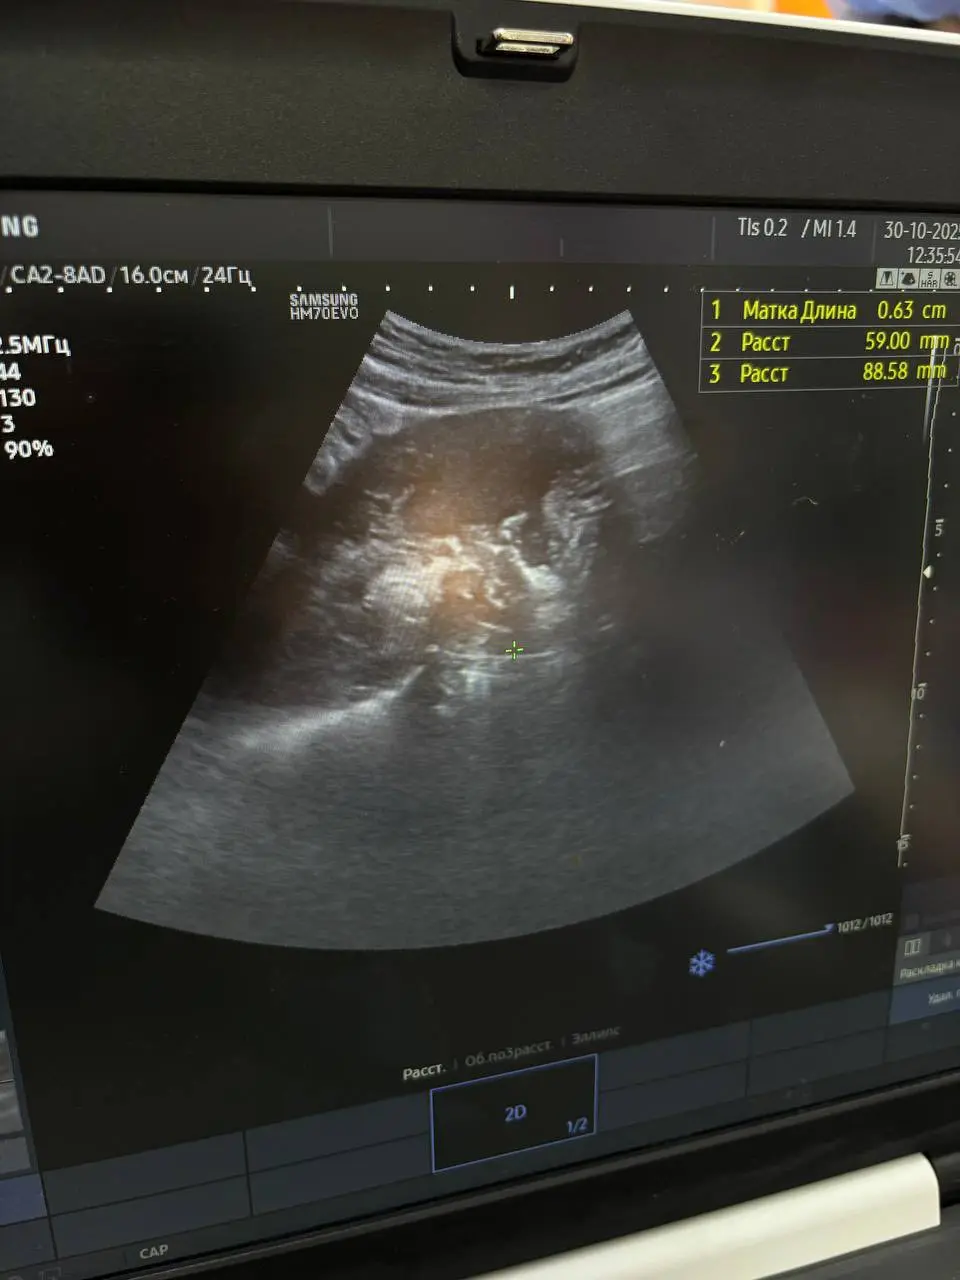

Днями до Вінницької обласної клінічної лікарні ім. М. І. Пирогова поступила 18-річна дівчина з матковою кровотечею.

Зазначають, що дівчина чотири місяці тому народила дитину. У дівчини в анамнезі, зокрема, епілепсія з частими нападами, хронічний гепатит С, лімфобластний лейкоз у минулому, ураження лімфовузлів і сирінгомієлія з ураженням лівої тім’яної ділянки головного мозку. У її випадку така кровотеча могла стати фатальною.

Так, гінекологи, анестезіологи та інтервенційні хірурги провели обстеження і в результаті провели два втручання:

– емболізацію судин матки – аби зупинити кровотечу без видалення органа;

– гострий кюретаж з евакуацією вмісту порожнини матки – для очищення порожнини матки після стабілізації кровотоку.

Таке поєднання дозволило зберегти не лише життя, а й репродуктивну функцію – дівчина має шанс у майбутньому знову стати мамою.

Фото – зі сторінки Вінницької обласної клінічної лікарні імені М. І. Пирогова